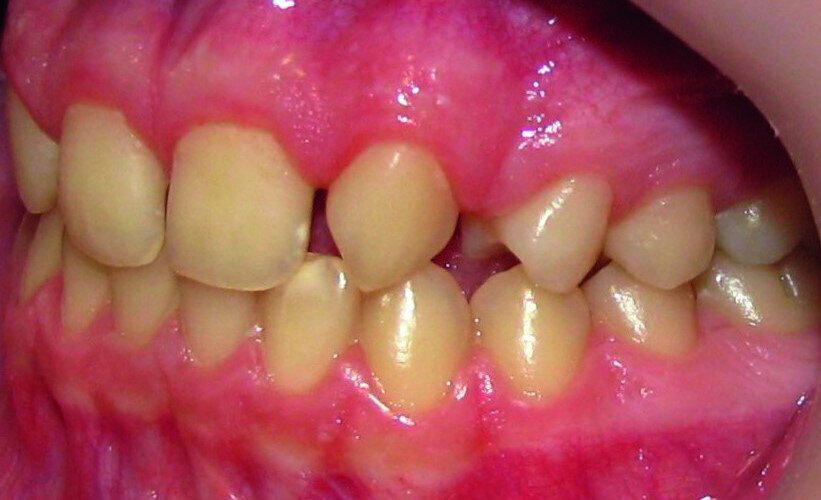

Then occlusal analysis (Figs. 11–21) was performed:

- Dental Class I.

- Insuficient overbite and overjet.

- Upper spacing due to the laterals agenesis (Fig. 18).

- Upper midline deviated to the right.